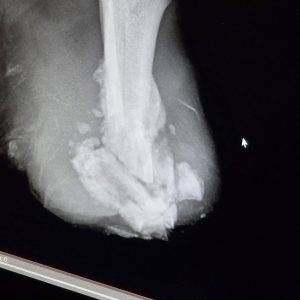

Sicher ist: Kein Zug hat ihm die Beine abgetrennt.

Die Verletzungen an beiden Hinterbeinen sind nicht zur gleichen Zeit entstanden. Es ist leider sehr wahrscheinlich, dass sie absichtlich verursacht wurden – unser Verdacht geht in Richtung einer Drahtschlinge.

Vor einigen ist unsere ungarische Tierschutzkollegin Betty schließlich zu ihm gefahren und hat ihn ins Krankenhaus gebracht, wo er sofort behandelt wurde. Einer der Stümpfe ist sogar auf dem Parkplatz der Klinik abgefallen, als er aus dem Auto gehoben wurde.